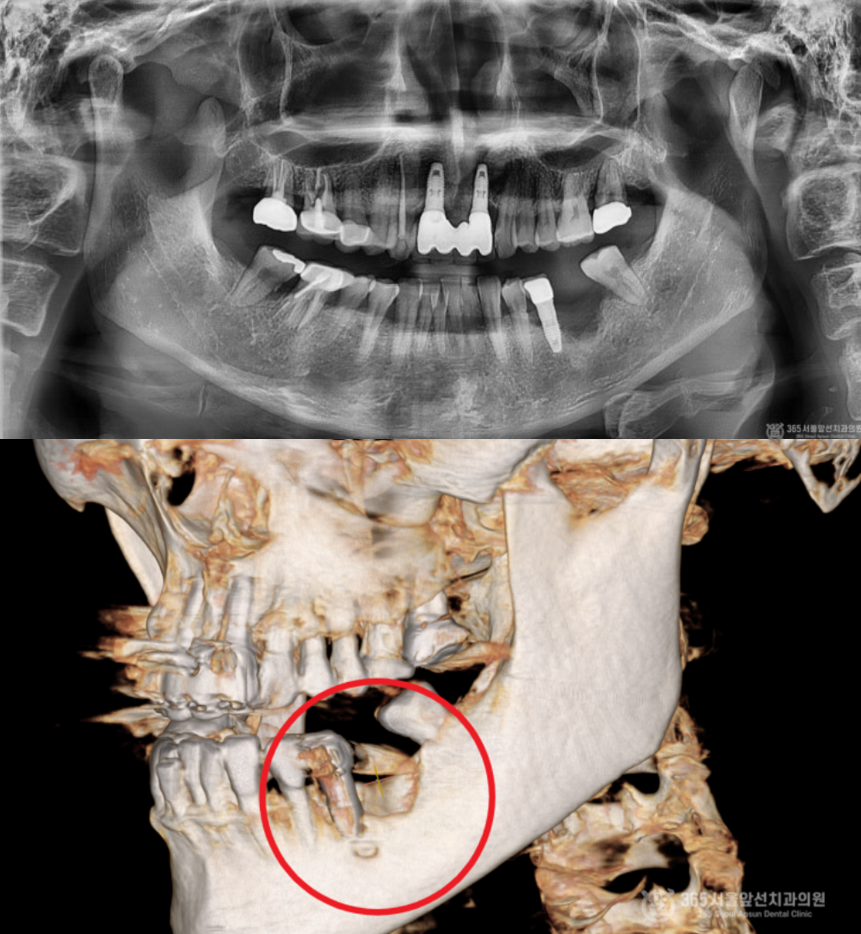

촬영일시 : 2024.05.19 X-ray 사진(위 이미지)상 오른쪽 아래(실제 입안에서는 왼쪽 아래 부위) 어금니 부위에 염증이 심하게 온 임플란트와 해당 임플란트 옆에 심한 치주염으로 발치가 된 자리가 보입니다. 또한 수술 전 CT 사진(아래 이미지) 을 찍어보니 마치 폭탄을 맞은듯하게 뼈가 웅덩이처럼 파여있는 모습이 관찰됩니다. 게다가 제거해야할 임플란트 아래쪽으로 신경이 지나가는 구멍이 있어서 수술을 할때 매우 주의해야하는 상황이었습니다. 두 자료를 를 종합해서 볼 때 뼈가 아래쪽으로 움푹 파여있어서 주변부위와 뼈의 높이를 맞춰주면서 염증에 이환된 임플란트를 제거하고 새로 식립하는 수술을 계획하였습니다.

촬영일시 : 2024.09.25 수술 후 수개월이 지나서 2차 수술을 진행한 모습이며, 이식한 뼈가 매우 잘되었음을 볼 수 있습니다.

더 정확한 확인을 위해 간석동치과잘하는곳 365서울앞선치과의원에서는 작은 엑스레이를 촬영하여 검사도 시행하였는데요. 매우 잘되었네요 ㅎㅎ 만족스럽습니다 ㅎㅎ 촬영일시 : 2024.10.01 보철물을 껴드리고 체크 과정에서 엑스레이를 촬영한 사진입니다. 결과가 매우 안정적입니다ㅎㅎ 오늘은 다양한 임플란트 골이식술들 중에서 가장 난이도가 높다고 알려진 수직골증대술과 상악동측방거상술을 동시에 시행한 환자분의 임플란트 치료 케이스를 소개해드렸는데요. 저희 간석동치과잘하는곳 365서울앞선치과의원에서는 임플란트 시행 건수 1만건 이상의 경험으로 난이도가 높은 임플란트 케이스도 자신있게 치료하고 있습니다 ㅎㅎ 이렇게 미국에서도 소문을 듣고 찾아주시니 제가 몸둘바를 모르겠습니다 ㅎㅎ 앞으로도 좋은 치료로 지역사회에 보답하는 365서울앞선치과가 되겠습니다 ! 감사합니다 ! [ 치료기간:2024년 5월19일 ~2024 10월 1일 ] ※ 365서울앞선치과의원의 모든 포스팅은 각 진료과 의료진이 직접 작성합니다. 365서울앞선치과의원 블로그의 임상 케이스 게시물은 환자분께 의학적으로 정확하고 상세한 정보를 드리기 위해 각 진료과 의료진이 직접 작성하며, 모든 증례 사진은 본원 의료진이 직접 시술한 증례를 촬영한 것으로, 의료법 제23조, 제56조에 의거하며 환자분의 동의를 얻어 포스팅에 사용하였습니다. 또한 해당 케이스는 본 환자분의 치료 결과이며, 환자 상태에 따라 치료의 결과는 달라질 수 있습니다. |